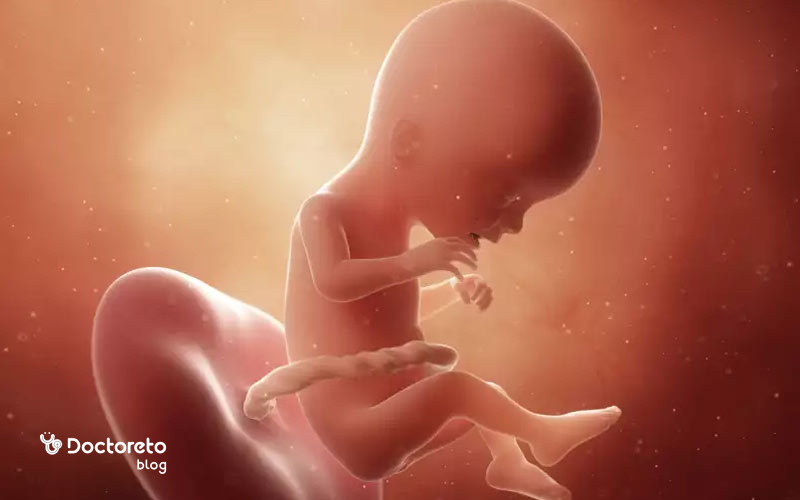

در هفته هفدهم بارداری، جنین حدود ۱۲ سانتیمتر طول و حدود ۱۰۰ تا ۱۴۰ گرم وزن دارد و بهسرعت در حال رشد است. بدن او حالا کشیدهتر و متناسبتر شده و سر نسبت به بدن کوچکتر به نظر میرسد. استخوانها و عضلات محکمتر شدهاند و جنین میتواند حرکات هماهنگتری مانند خمکردن دست و پا یا چرخیدن انجام دهد. چربی زیرپوستی در حال شکلگیری است و پوست جنین با مادهای سفید و چرب به نام ورنیکس (Vernix caseosa) پوشیده میشود تا از او در برابر مایع آمنیوتیک محافظت کند. گوشها و چشمها در جای طبیعی خود قرار گرفتهاند و ریهها، قلب و کلیهها فعالتر شدهاند. در سونوگرافی این هفته معمولاً میتوان حرکات، ضربان قلب و حتی واکنشهای چهرهای خفیف جنین را مشاهده کرد.

در هفته هفدهم بارداری جنین چه شکلی است؟

هفته هفدهم حاملگی جنین به اندازه یک انار میشود. همانطور که گفته شد اندازه جنین از سر تا باسن حدود ۱۳ سانتیمتر است. جنین در رحم حرکت میکند و احتمال دارد این حرکات را احساس کنید. اگرچه چشمان جنین بسته است، اما میتواند آنها را حرکت دهد. دهان جنین باز و بسته میشود،شنوایی شروع به تکامل میکند و پاسخ به صداهای بیرونی معمولاً در هفتههای بعد واضحتر میشود.

جنین شما در این مرحله حدود ۱۴۰ گرم وزن دارد و طولش نزدیک به ۱۳ سانتیمتر است؛ تقریباً به اندازه کف دست شما. چربی بدن او در حال شکلگیری است و تا پایان بارداری بهتدریج افزایش پیدا میکند.